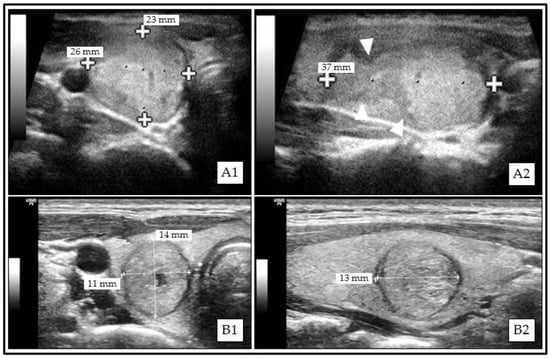

All TNs were classifiable according to Kwak-TIRADS, ACR TI-RADS, and Korean-TIRADS. A total of 3 (0.2%, 1 malignant) and 135 (11.1%, 16 malignant) TNs could not be classified using EU-TIRADS and ATA Guidelines, respectively (Figure 1). The RSS classification results are displayed in Figure 2.

Figure 1. Examples of thyroid nodules (TNs) that could not be classified according to American Thyroid Association (ATA) Guidelines. (A1) (transversal)/(A2) (sagittal): Solid isoechoic papillary thyroid carcinoma (PTC) with irregular margins (A2, white triangle markers). (B1) (transversal)/(B2) (sagittal): Mainly solid isoechoic benign (Bethesda II) thyroid nodule (TN) with taller-than-wide (TTW) shape.